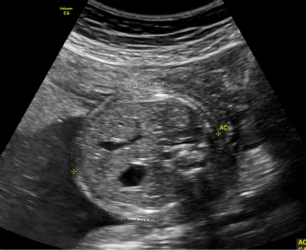

提高人口素质,控制人口质量是我国计划生育重要国策。减少缺陷儿的出生,生一个健康的宝宝是每一个家庭和全社会都在关注的问题,也是所有从事围产期保健工作者努力的方向。超声诊断由于其无创、无辐射、安全、方便、可动态的观察胎儿各器官的结构,目前已广泛应用于产前胎儿检测工作中,是重要的产前诊断影像手段之一。

2.妊娠18周~24周超声检查;主要进行胎儿结构畸形的系统筛查。此阶段是观察胎儿结构和诊断胎儿畸形黄金时段,我们建议所有孕妇在此阶段务必接受一次超声检查。

2.妊娠18周~24周超声检查:主要进行胎儿结构畸形的系统筛查。此时期胎儿各器官已发育成熟,系统产前超声检查可记录胎儿各器官结构包括头颅、面部、胸腹腔、心脏、肝脏、双肾、肢体及胎盘等结构,可发现大多数胎儿结构畸形。此阶段是观察胎儿结构和诊断胎儿畸形黄金时段,我们建议所有孕妇在此阶段务必接受一次超声检查。

只需要选择高档二维彩色系统产前超声检查,它包括胎儿结构29张图片,主要观察胎儿发育与结构是否正常。